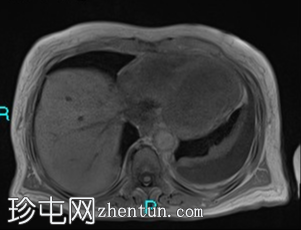

冠状位

T2加权像

冠状位T2加权像

胰腺钩突附近可见边界不清的肿块,T2加权像呈不均匀中等信号,弥散受限明显。肿块大小为4.1 x 5 x 3 cm(前后径 x 横径 x 头尾径)。伴有胰管扩张,直径约6 mm。

肝脏可见多个大小不一的可疑病灶(从亚厘米级到2厘米不等)。T2加权像呈高信号,弥散受限明显。

远端胆总管突然变窄,但未完全阻塞。

胰腺周围可见多发囊性病变,部分与主胰管相连,提示胰腺导管内乳头状黏液性肿瘤(IPMN)。

双侧胸腔积液,左侧较多。